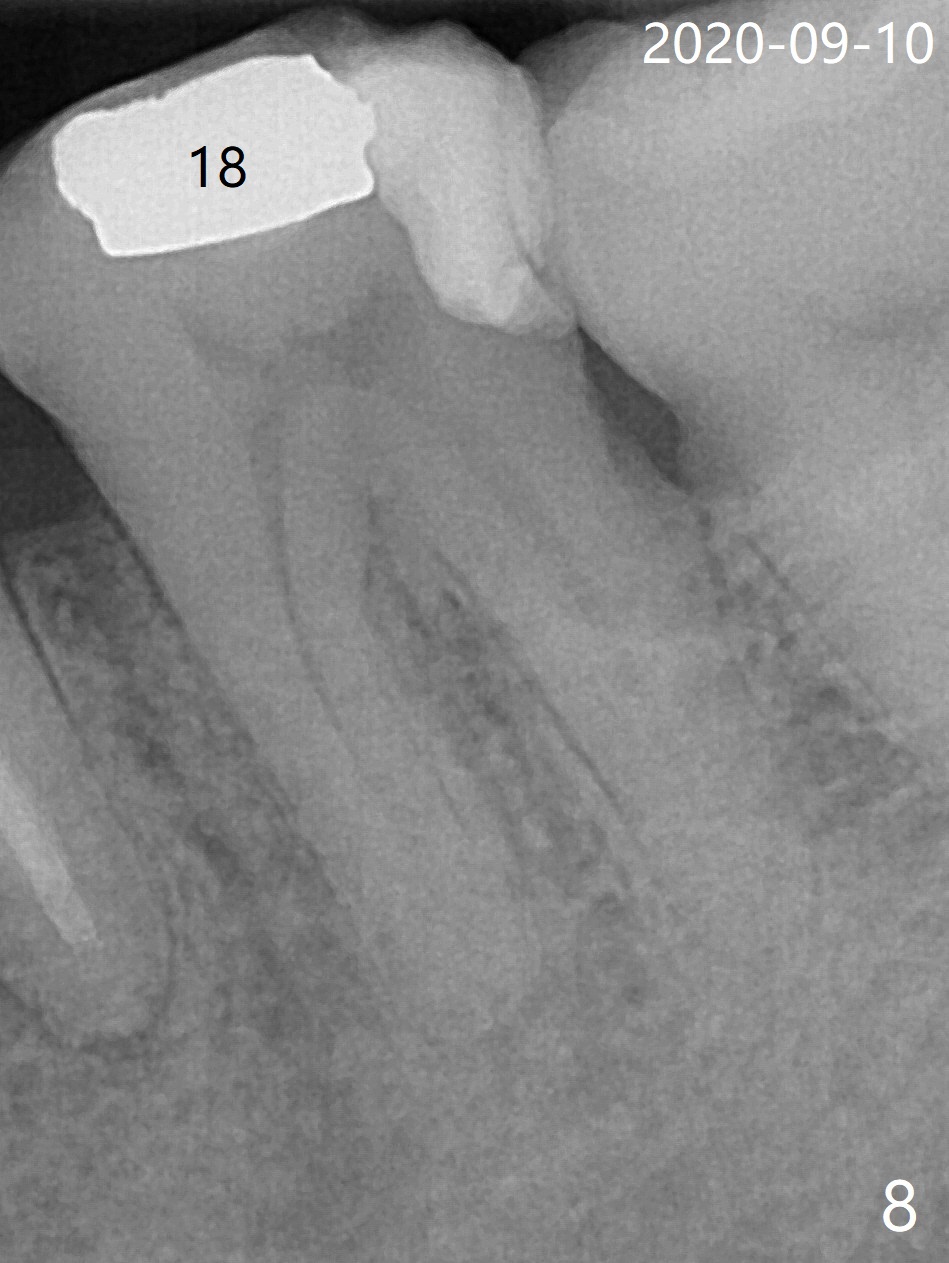

Designed osteotomy depth is 7.3 mm IS drill with 4 rings at #15. In fact osteotomy is created using 2.2 mm drill with 2 rings (sinus membrane barely visible from the osteotomy) and 3-4 mm ones with 3 rings. With an amalgam carrier of bone graft, sinus lift is initiated with 4x9 mm dummy implant (Fig.1). After loaded with totally 5 amalgam carriers of bone graft repeatedly with the 4x9 mm dummy implant, a 5x9 mm implant is placed with ~ 25 Ncm. After insertion of a 6x4(2) mm abutment, sticky bone cut into pieces (Fig.2) is inserted to peri implant space (Fig.3 *), followed by PRF and an immediate provisional. The latter dislodges 7 days postop; the socket starts to heal (Fig.4); the bone graft seems to be fixed in place. The provisional is reseated (no cement, Fig.5) without fear of its dislodgement again. The patient returns for cleaning 1 year 7 months postop (Fig.6,7). The socket heals, while the abutment is incompletely seated (Fig.7 <). Percussion at #18 disappears post RCT, whereas periapical radiolucency appears post RCT (compare Fig.8,9). When the 6x4(2) mm incompletely seated abutment is removed, the implant well is dirty. The smaller abutment with longer cuff is seated fully (Fig.10).